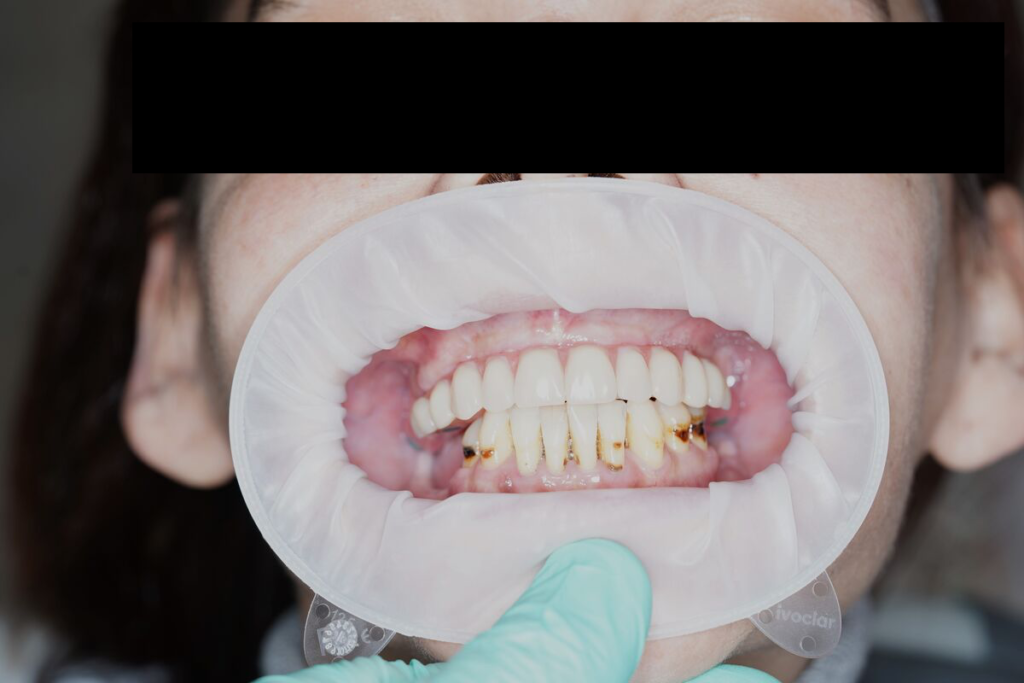

Výsledky, které mluví za vše

- fotografie před/po

Technika All-on-X — I. fáze

Technika All-on-X — II. fáze